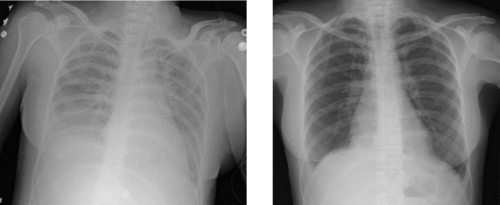

A chest x-ray of transfusion-related acute lung injury (left) which led to ARDS. Right is a normal X-ray before the injury.

Medical imaging

Radiologic imaging has long been a criterion for diagnosis of ARDS. Original definitions of ARDS specified that correlative chest X-ray findings were required for diagnosis, the diagnostic criteria have been expanded over time to accept CT and ultrasound findings as equally contributory. Generally, radiographic findings of fluid accumulation (pulmonary edema) affecting both lungs and unrelated to increased cardiopulmonary vascular pressure (such as in heart failure) may be suggestive of ARDS.[17]